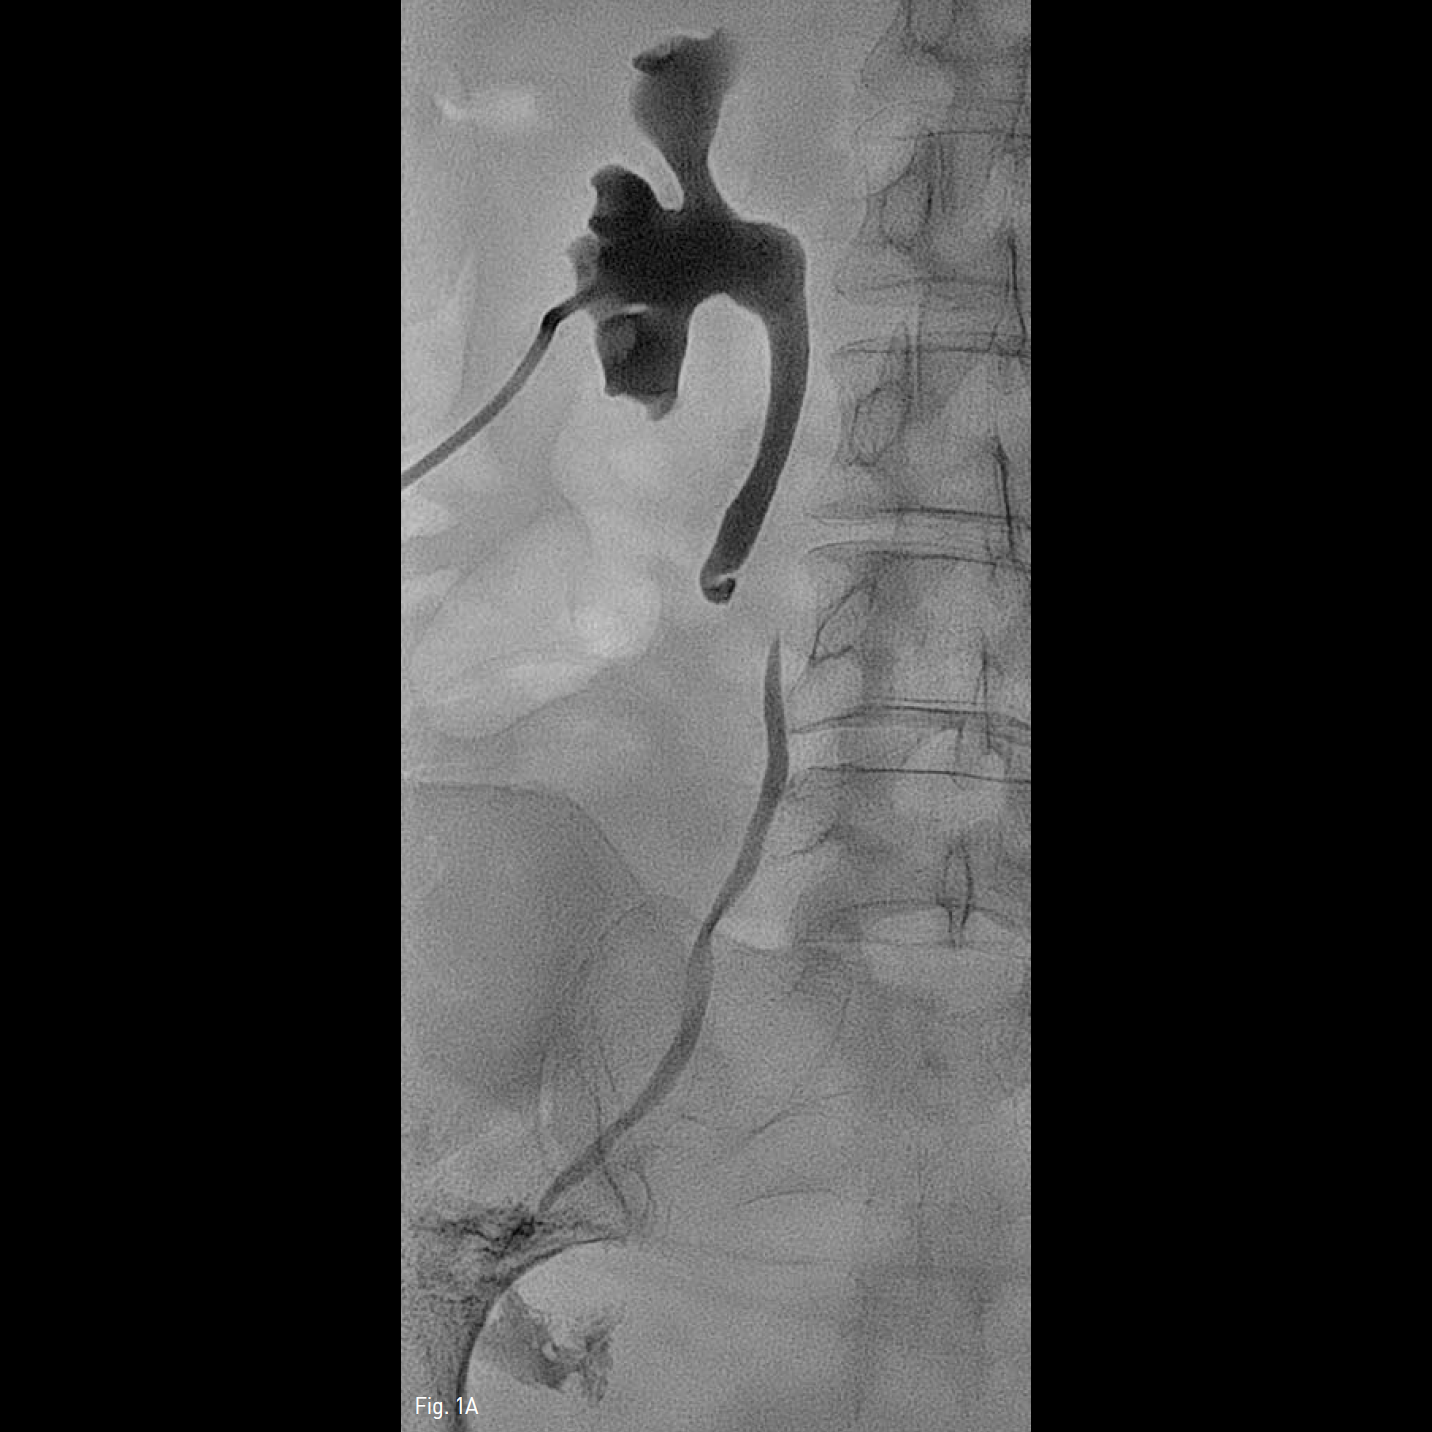

진입되었다. 방광 내로 5-Fr Kumpe catheter와 0.035 인치 유도철사를 삽입하여 아래쪽에서 역행성으로 요관에 유도철사 진입을 시도하였으나 여시 유도철사가 후복막으로 빠졌다. 경피적 신루설치술 부위를 통해 하행성으로 Gooseneck snare(ev3, Plymouth, MN, USA)를 삽입하여 후복막에 진입시킨 후 방광을 통해 역행성으로 유도철사를 삽입 시켜 후복막으로 진입시켰다. 이 유도철사를 하행성으로 삽입한 Gooseneck snare로 포획하여(Fig. 1C) 경피적 신루설치술 부위로 제거하고(Fig. 1D), 이 유도철사를 따라 성공적으로 7-Fr, 28cm double J stent(Cook, Bloomington, IN, USA)를 삽입한 후 PCN 도관을 설치하고(Fig. 1E) 시술을 미쳤다.

Fig. 1C, D, E

C-D. Terumo guide wire which was inserted through the urinary bladder was captured by a Gooseneck snare at retroperitoneum and removed through PCN tract

E. Final fluoroscopic image shows adequate placement of double J stent.